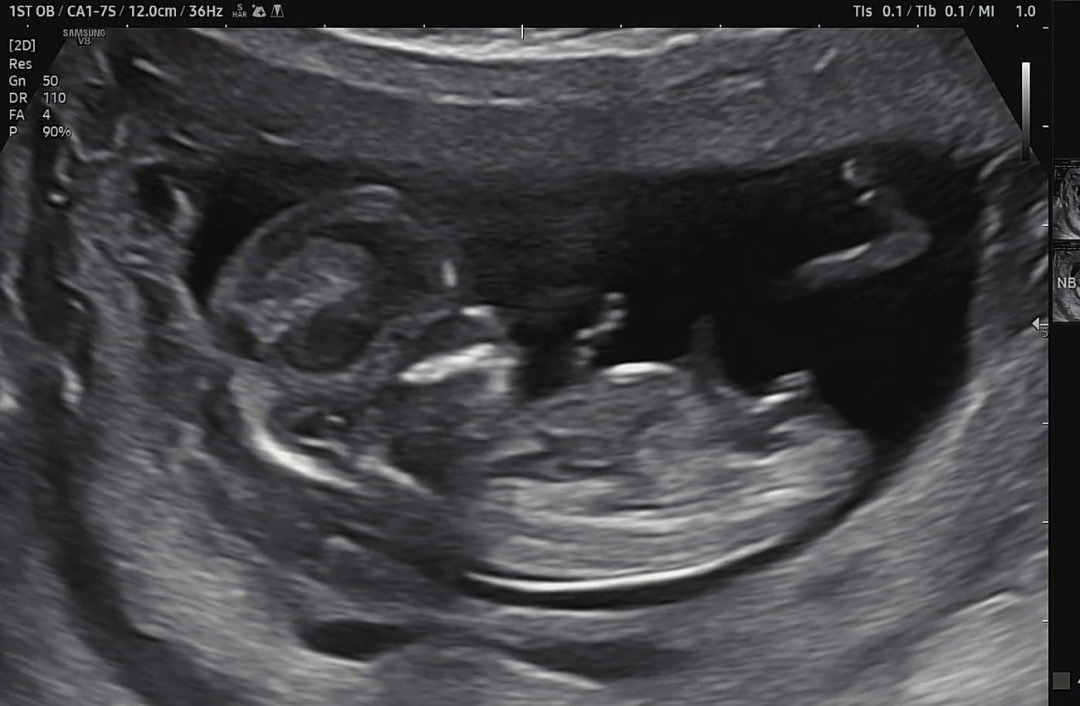

12주 6일 각도법 봐주세요!

초음파쌤은 아들같다던데🤔 위로 솟은 느낌이긴 하네용 ㅎㅎ